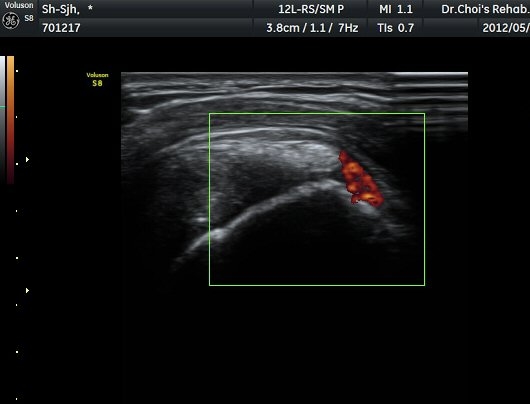

Á߸³»óÅ ¾î±ú ¾Õ Ⱦ´Ü¸é°Ë»ç¿¡¼­ À̺ειڱ٠ÁÖÀ§¿¡ ¼ö¾×Àú·ù°¡ °üÂûµÇ°í(»çÁø 1) ÆÄ¿öµµÇ÷¯

°Ë»ç¿¡¼­ Ç÷·ùÁõ°¡°¡ °üÂûµÈ´Ù(»çÁø 2). À̵ιڱ٠Á¾´Ü¸é°Ë»ç¿¡¼­µµ °Ç ÁÖÀ§ ¼ö¾×Àú·ù°¡ È®ÀÎ